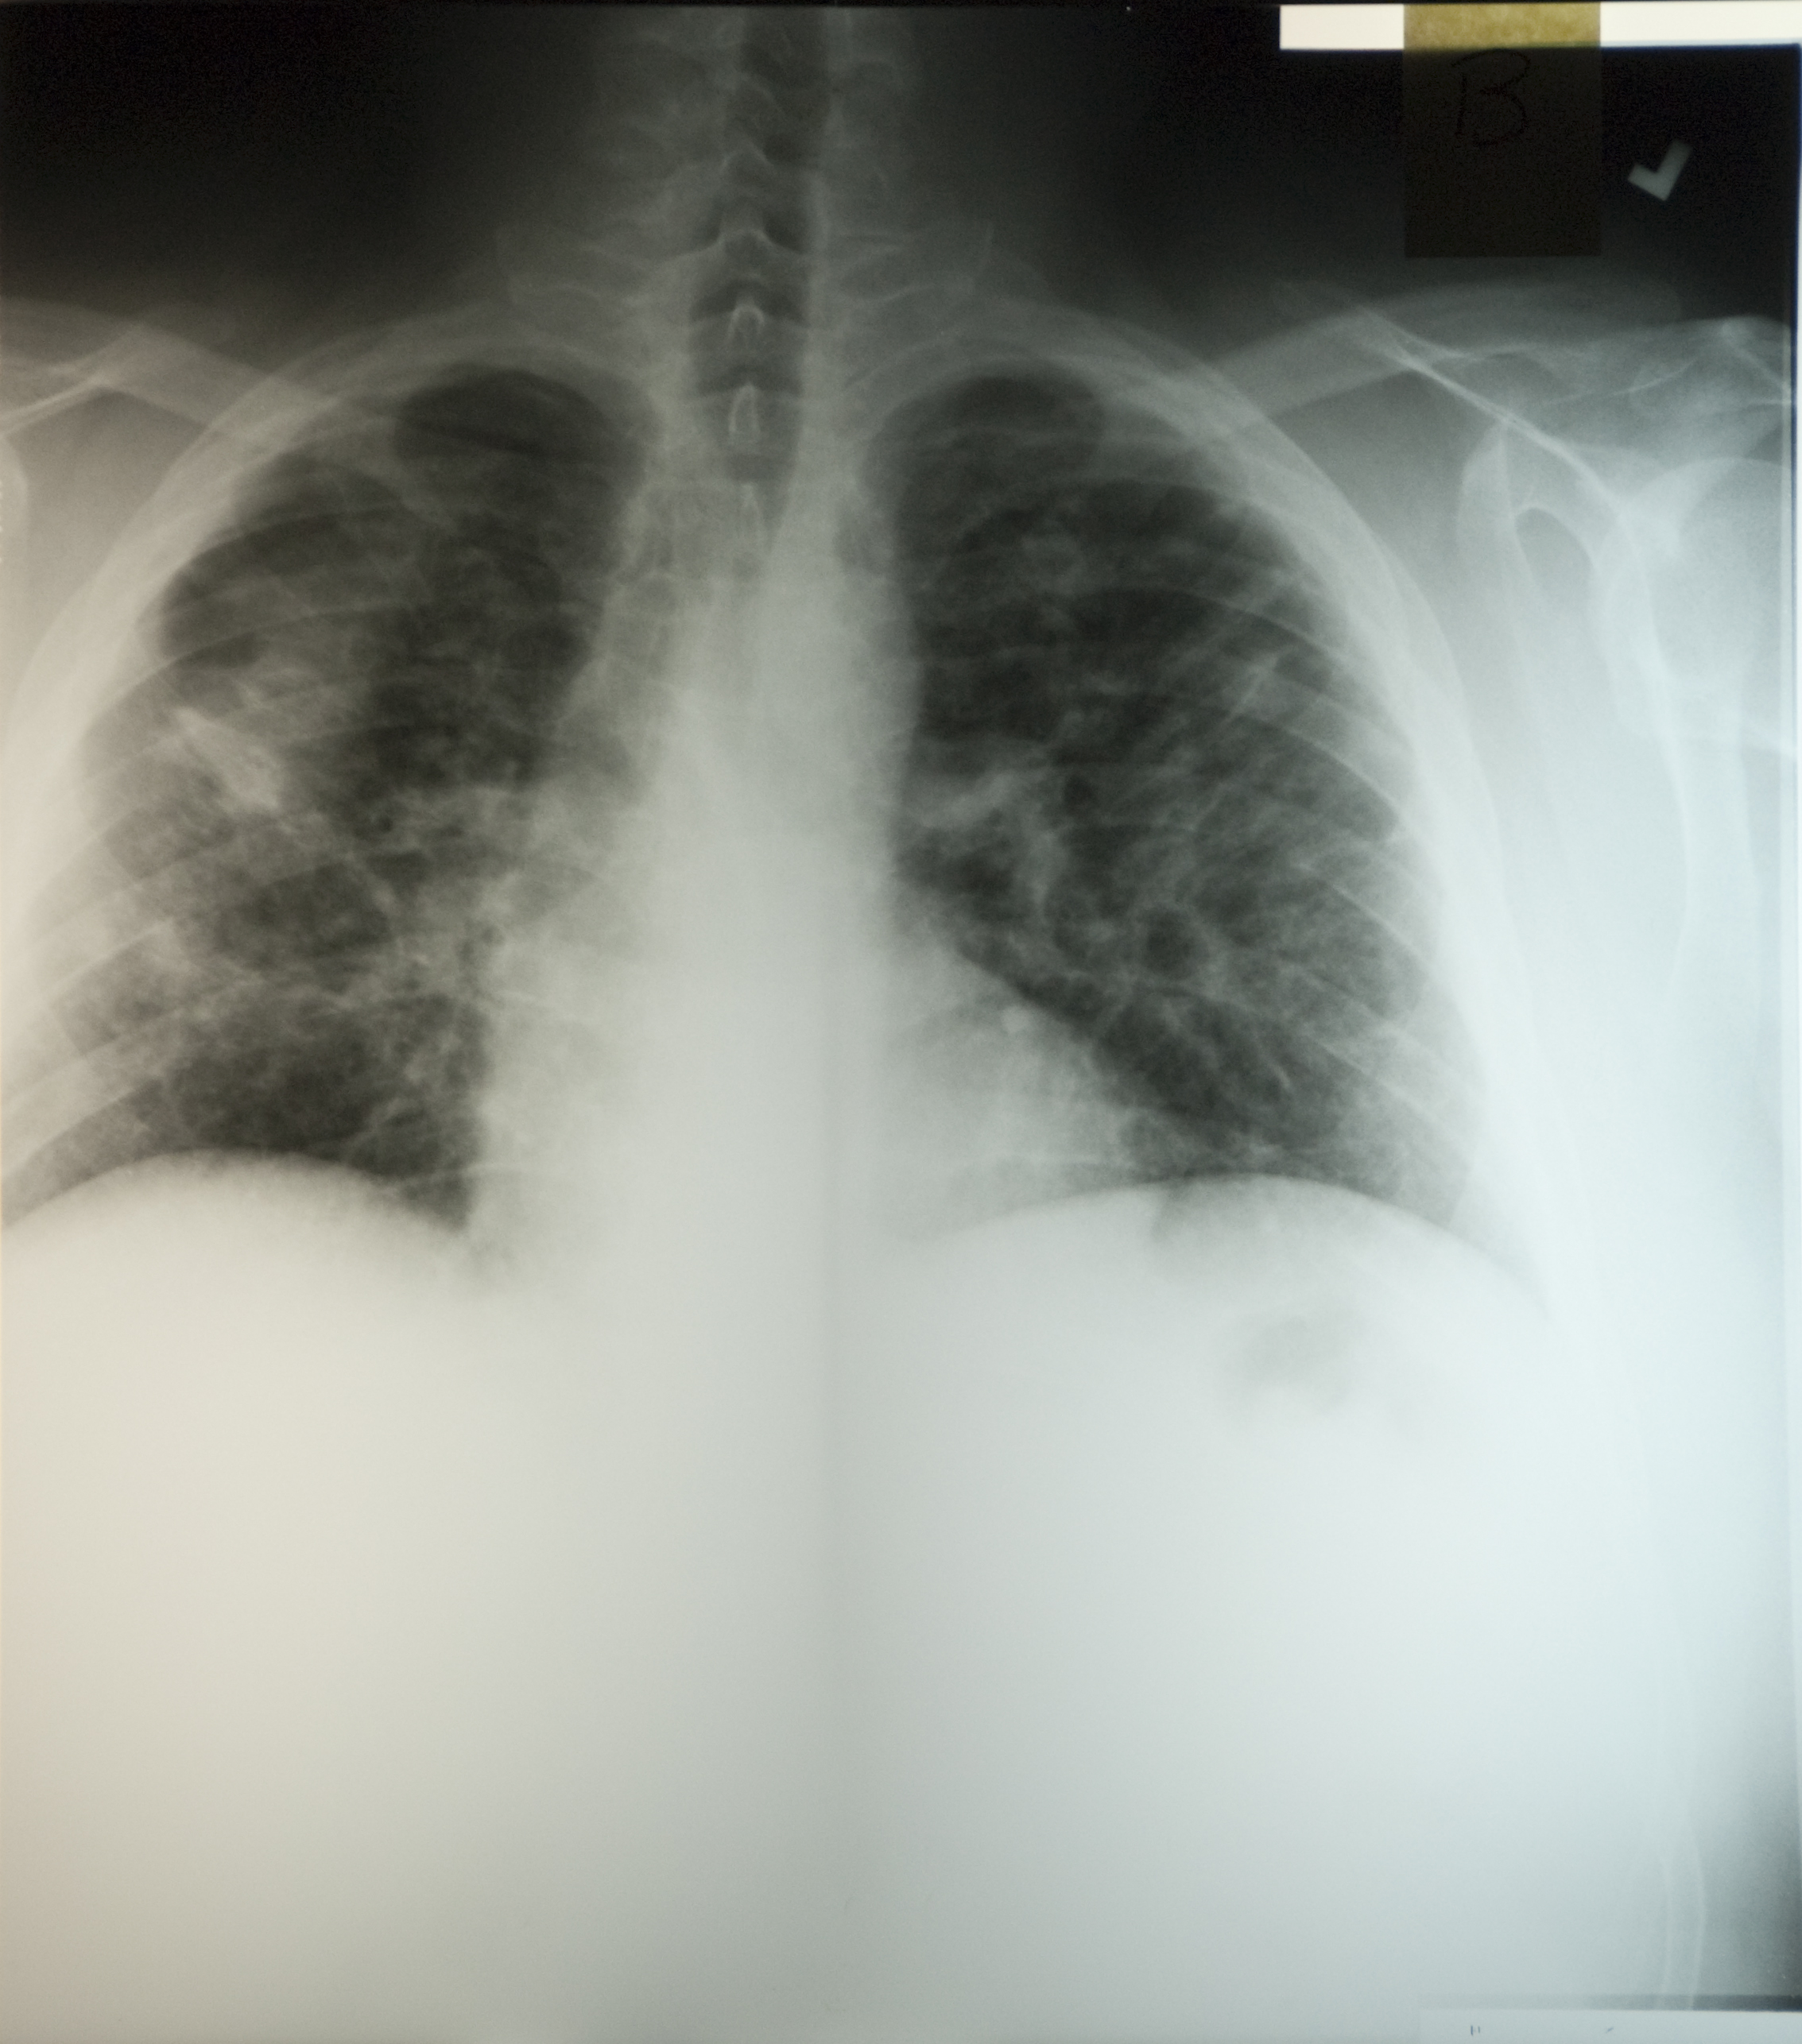

A chest radiograph was taken at that time (Figure 1.3).

Figure 1.3

Both coal and silica dust exposures trigger inflammation of the airways and the interstitium, and pneumoconiosis can continue to progress for years after termination of all dust exposure (1). This is one reason why primary prevention through dust control is critical. Inflammatory nodules can coalesce to form PMF (also called complicated pneumoconiosis), which is recognized on the chest radiograph as one or more lesions 10mm in diameter or greater. After PMF develops, the fibrosis and associated emphysema often progress even without further dust exposure, as was the case with this patient. Adjacent lung parenchyma is pulled towards the lesions, which most typically occur in the upper lung. The large airways are distorted as lung volume is lost and lung function may show obstructive and/or restrictive impairments.